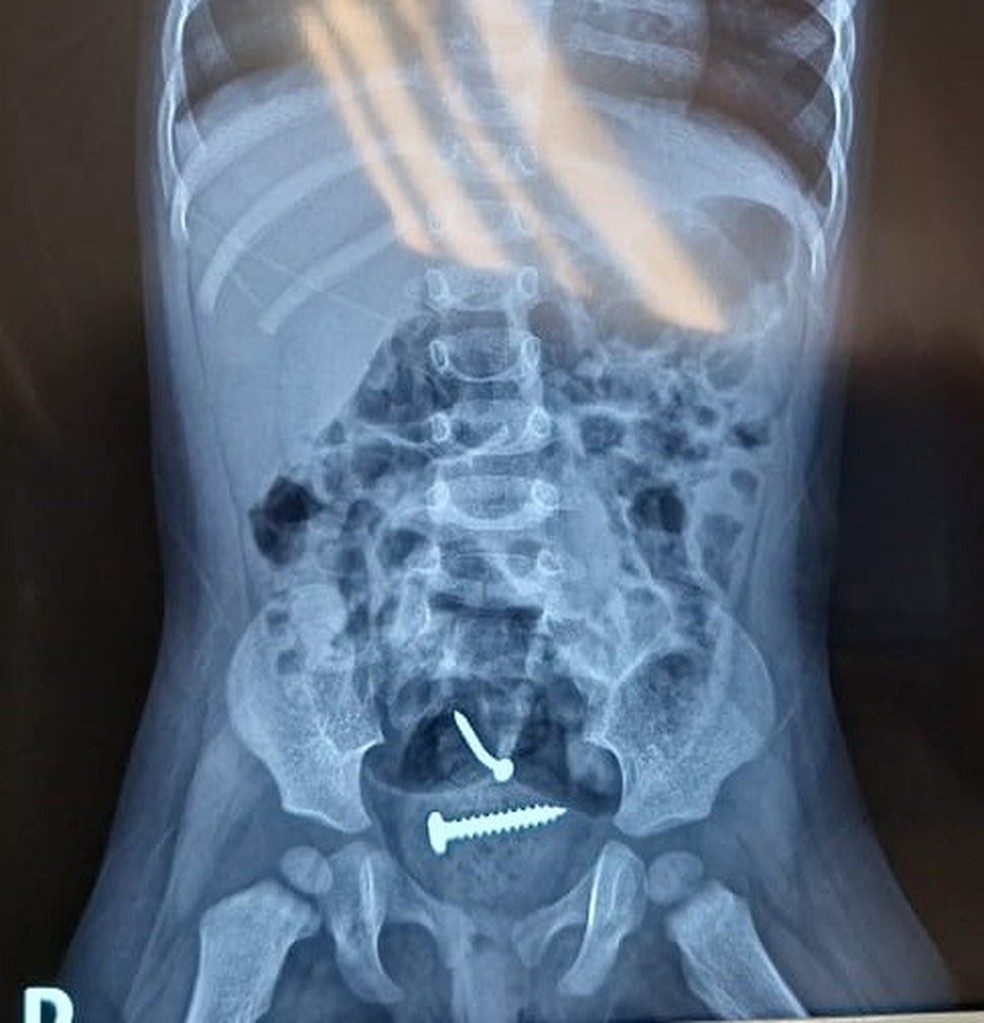

Médicos avaliam como retirar parafusos do corpo de bebê; pai foi preso suspeito de violência sexual e agressões

Os médicos encontraram dois parafusos ao fazer um exame de raio-x da criança e ainda não se sabe como os objetos foram parar no corpo dela